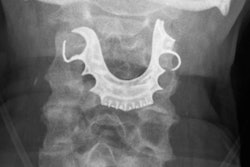

Oropharyngeal carcinoma patients treated with intensity-modulated proton therapy (IMPT) were half as likely to need feeding tubes compared to patients treated with intensity-modulated radiation therapy (IMRT).

The study from the MD Anderson Proton Therapy Center, presented on September 25 at the American Society for Radiation Oncology (ASTRO) annual meeting in Atlanta, also found that toxicity levels in oropharyngeal carcinoma patients treated with IMPT were much lower than in patients treated with IMRT.

Based on the results, lead researcher Dr. Steven J. Frank, associate professor of radiation oncology at MD Anderson, and colleagues stated that proton therapy may offer quality-of-life benefits for patients with tumors occurring at the back of the throat.

The researchers evaluated 25 oropharyngeal carcinoma patients treated with IMPT and 25 treated with IMRT. Five patients (20%) treated with IMPT required the use of feeding tubes, compared with 12 patients (48%) treated with IMRT.

IMPT patients were also spared from other serious side effects caused by the toxicity of IMRT, such as vomiting, nausea, hearing problems, and inflammation and ulceration of the digestive track. In addition, patients could better sustain their nutrition and hydration levels, often leading to faster recovery during and after treatment.

Based on the findings, MD Anderson has initiated a randomized phase II/III trial of IMPT versus IMRT for the treatment of oropharyngeal cancer. The institution plans to enroll 360 patients in the trial over the next five years.